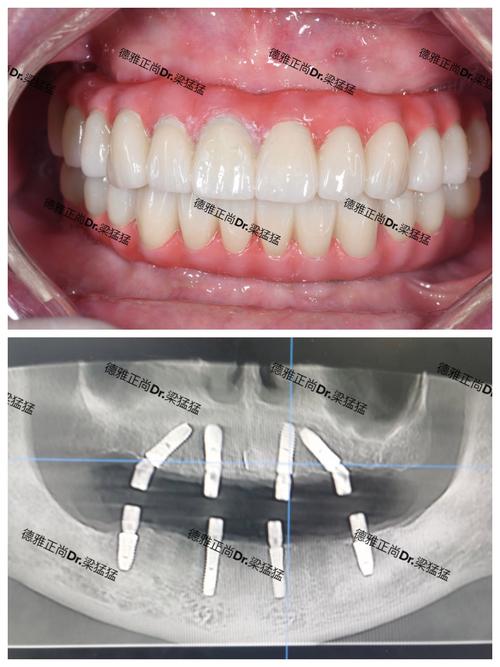

种植牙的费用主要由三部分组成:种植体、基台、牙冠,以及前期的检查、设计、手术和后期维护,种植体作为核心材料,其材质、品牌、表面处理技术直接决定了成本上限,目前市面上主流的种植体多为纯钛或钛合金材质,这类生物相容性极佳的材料能与人骨紧密结合,但纯钛的加工工艺复杂,尤其是进口高端品牌,如瑞士的Straumann(士卓曼)、瑞典的Nobel Biocare(诺贝尔),其研发历史长达数十年,临床数据丰富,表面处理技术(如SLA活性表面)能显著提高骨结合速度和成功率,这类种植体的单颗价格普遍在6000-12000元不等,而基台作为连接种植体和牙冠的“桥梁”,材质也有钛基台、全瓷基台之分,全瓷基台美观性更好,尤其适合前牙修复,价格比钛基台高出2000-5000元,牙冠部分,根据材质不同,有全金属、烤瓷、全瓷三种,全瓷牙冠(如氧化锆)因其美观、生物相容性好、不易过敏,成为目前的主流选择,单颗价格在3000-8000元不等,仅这三项核心材料,进口高端组合的总价就已接近甚至超过万元,若加上术前CBCT检查、数字化导板设计、手术费、麻醉费等,整体费用自然“水涨船高”。

种植牙并非简单的“在牙槽骨里拧个钉子”,而是一项融合了医学、材料学、影像学的精密手术,医生需要通过CBCT获取患者颌骨的三维数据,设计种植体的植入位置、角度和深度,避免损伤神经、血管;对于牙槽骨条件不佳的患者(如骨量不足、骨密度低),还需进行植骨、上颌窦提升等附加手术,这些手术难度更高,耗材成本也更高(如骨粉、骨膜费用约2000-5000元/颗),数字化种植技术的普及(如3D打印导板、动态导航系统)能显著提高手术精准度,减少创伤,但这些设备本身价格昂贵(一台口腔CBCT可达数十万至数百万),其使用成本也会分摊到患者费用中,更重要的是,种植医生的经验和技术水平直接影响手术成功率——经验丰富的医生能应对复杂的口腔状况,减少并发症(如种植体周围炎、骨吸收),而培养一名成熟的种植医生需要10年以上的临床积累和持续学习,其技术价值也是费用的重要组成部分。